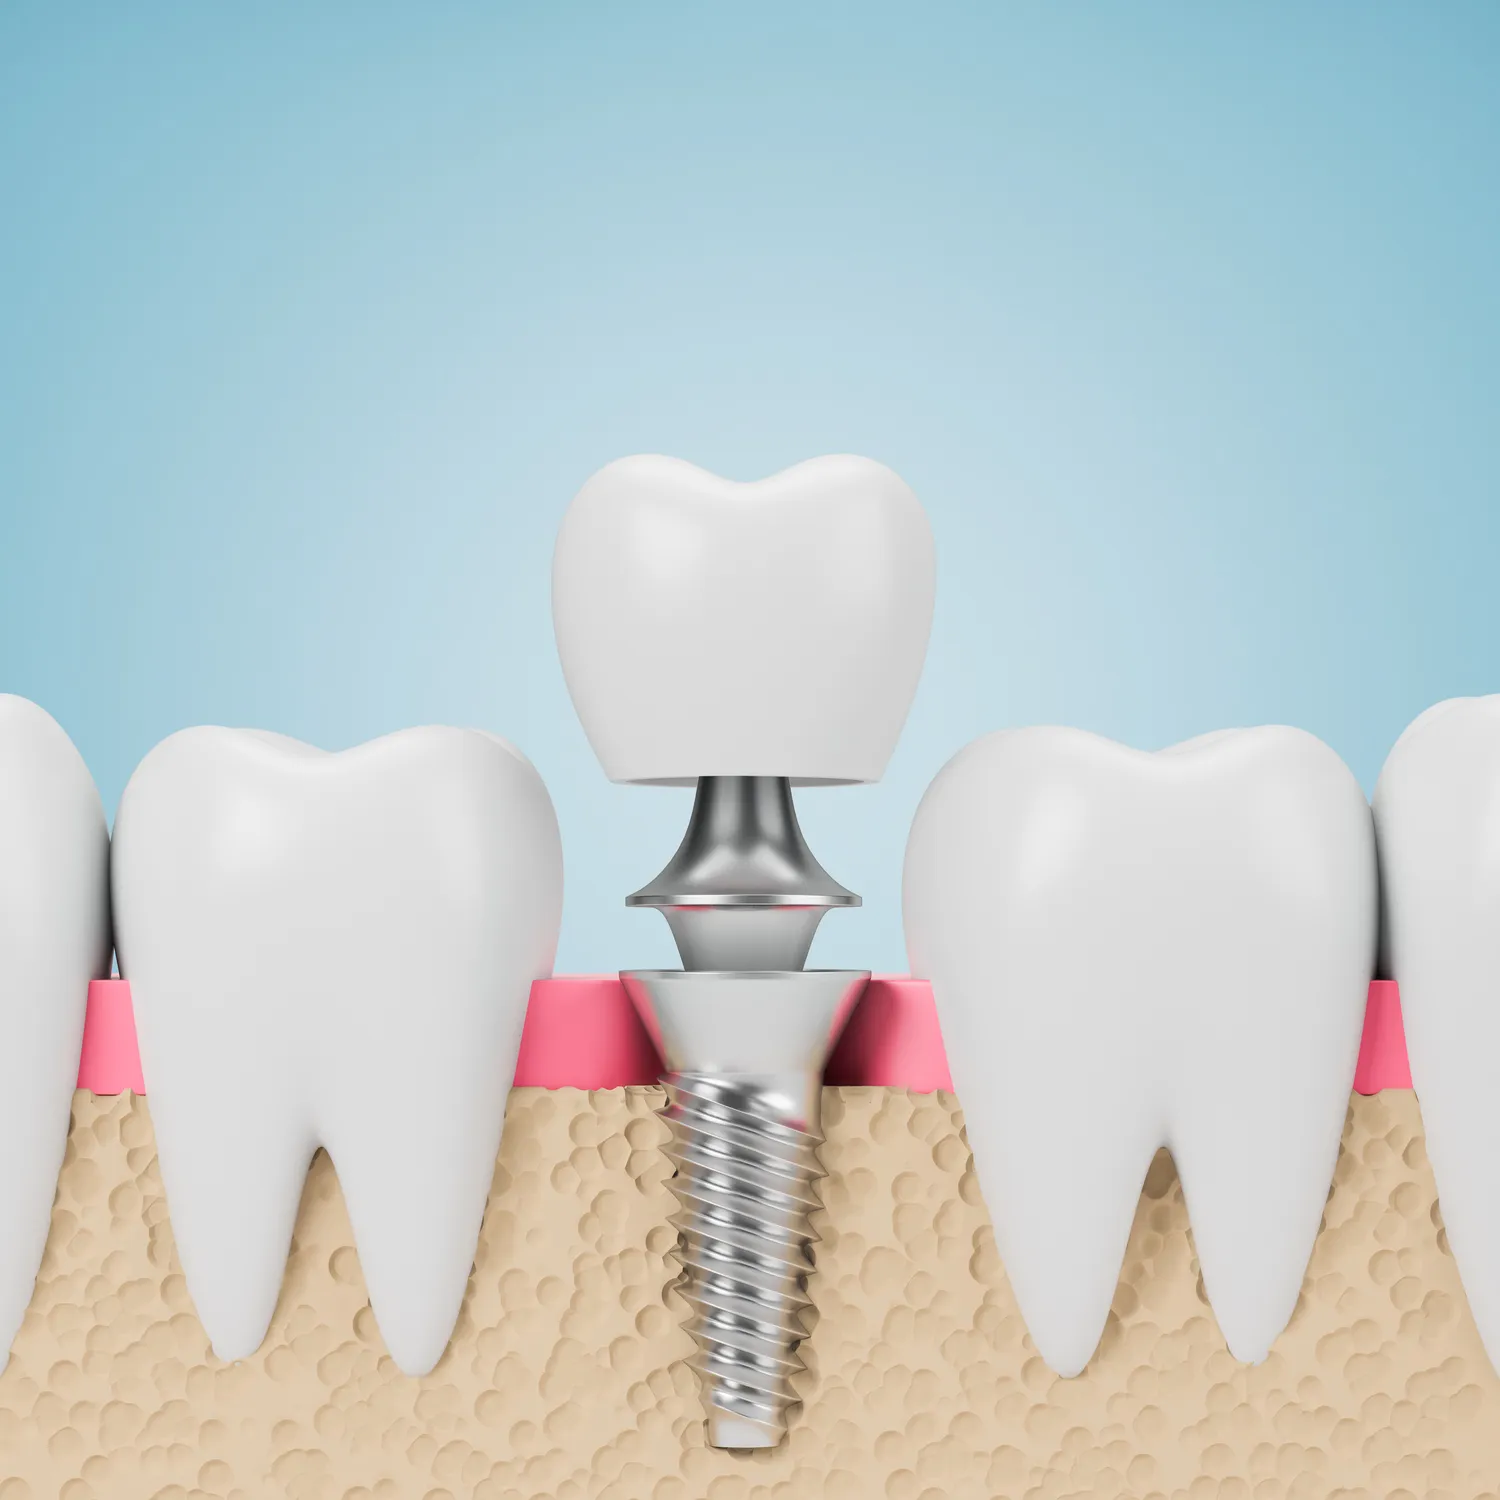

Następnie przystępuje się do zabiegu chirurgicznego wszczepienia implantu. Jest to procedura wykonywana zazwyczaj w znieczuleniu miejscowym, dzięki czemu jest bezbolesna. Po przygotowaniu łoża kostnego, implant jest delikatnie wprowadzany do kości. Po zabiegu pacjent otrzymuje zalecenia dotyczące higieny jamy ustnej i ewentualnego stosowania leków przeciwbólowych. Kolejnym etapem jest okres gojenia, który trwa zazwyczaj od kilku tygodni do kilku miesięcy. W tym czasie implant integruje się z kością, tworząc stabilne podparcie dla przyszłego uzupełnienia protetycznego. Po zakończonym procesie osteointegracji, na implancie montowany jest łącznik, a następnie indywidualnie dopasowana korona protetyczna, która przywraca pełną funkcjonalność i estetykę uśmiechu.